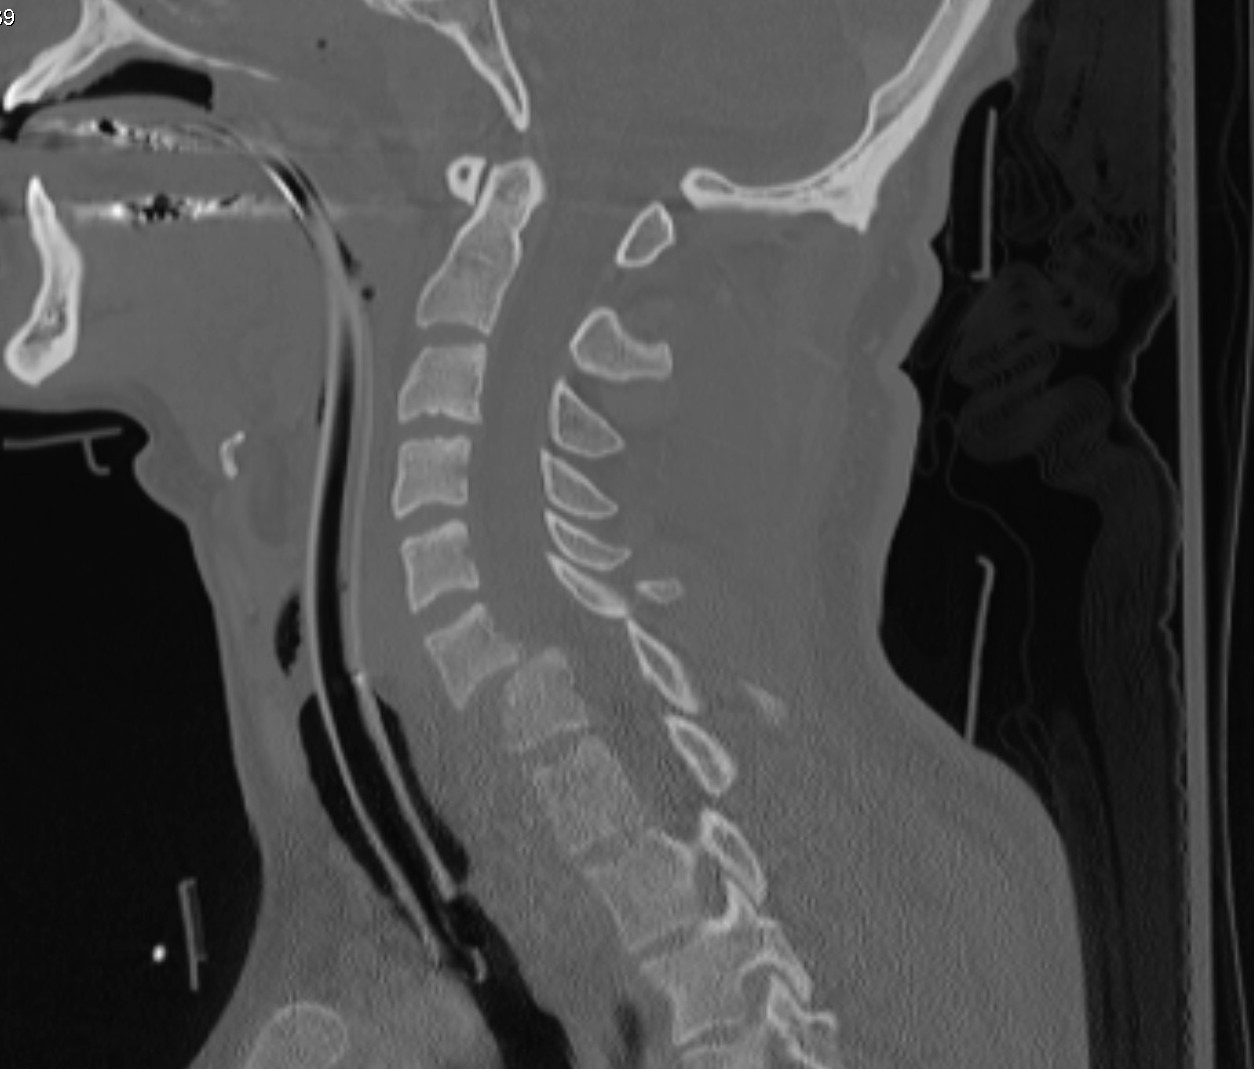

Differentiating Cervical Myelopathy From Radiculopathy r/sportsmed

Cervical myelopathy, radiculopathy Neuroland 2G Cervical Radiculopathy Reddit Cervical radiculopathy, commonly called a pinched nerve, occurs when a nerve in the neck is compressed or irritated where it branches away from the spinal cord. This may cause pain that. Cervical radiculopathy is a living nightmare. I went to urgent care yesterday, which is where i was diagnosed with a trapezius strain and prescribed prednisone and flexeril, but i'm. Cervical Radiculopathy Reddit.